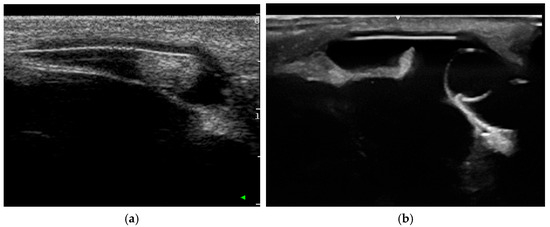

Intraocular Tumors in Horses: Diagnosis, Tumor Classification, Oncologic Assessment and Therapy

Intraocular neoplasia in horses is rare and only few case reports and small case series exist. Intraocular neoplasia has various clinical signs and includes important differential diagnoses in ocular disease. This narrative review of the current literature aims to provide a clinically relevant overview and classification of intraocular tumors in horses and adds a comparative oncological perspective concerning diagnosis, treatment and future considerations. The available clinical and imaging examination techniques allow for a reliable and differentiated investigation of the tumor, even in the standing horse, using high-frequency ultrasound or optical coherence tomography, which have gained importance in equine ophthalmology. Sectional imaging techniques, in particular computed tomography, are suitable for the examination of the peribulbar, retrobulbar and orbital structures. Differentiated diagnostics including precise tumor staging (TNM: tumor, node, metastasis) are essential for a general prognostic and therapeutic assessment. The embryologic and anatomic tissue origin of the neoplasm is the basis for clinicopathologic classification. Medulloepithelioma and uveal melanocytic neoplasia are the most common intraocular tissue formations occurring in horses. Whereas melanocytic neoplasia of the iris can be treated surgically, neuroepithelial tumors regularly lead to bulbus extirpation. Other primary intraocular neoplasms are sporadically reported, as well as intraocular metastasis of systemic neoplasia. Chemotherapy and radiation therapy are not currently used to treat intraocular neoplasia in horses and need to be further investigated, especially regarding the latest developments in human and small animal medicine. In addition, horses and dogs may serve as models for human oncologic research. Full article

Show Figures

Figure 1